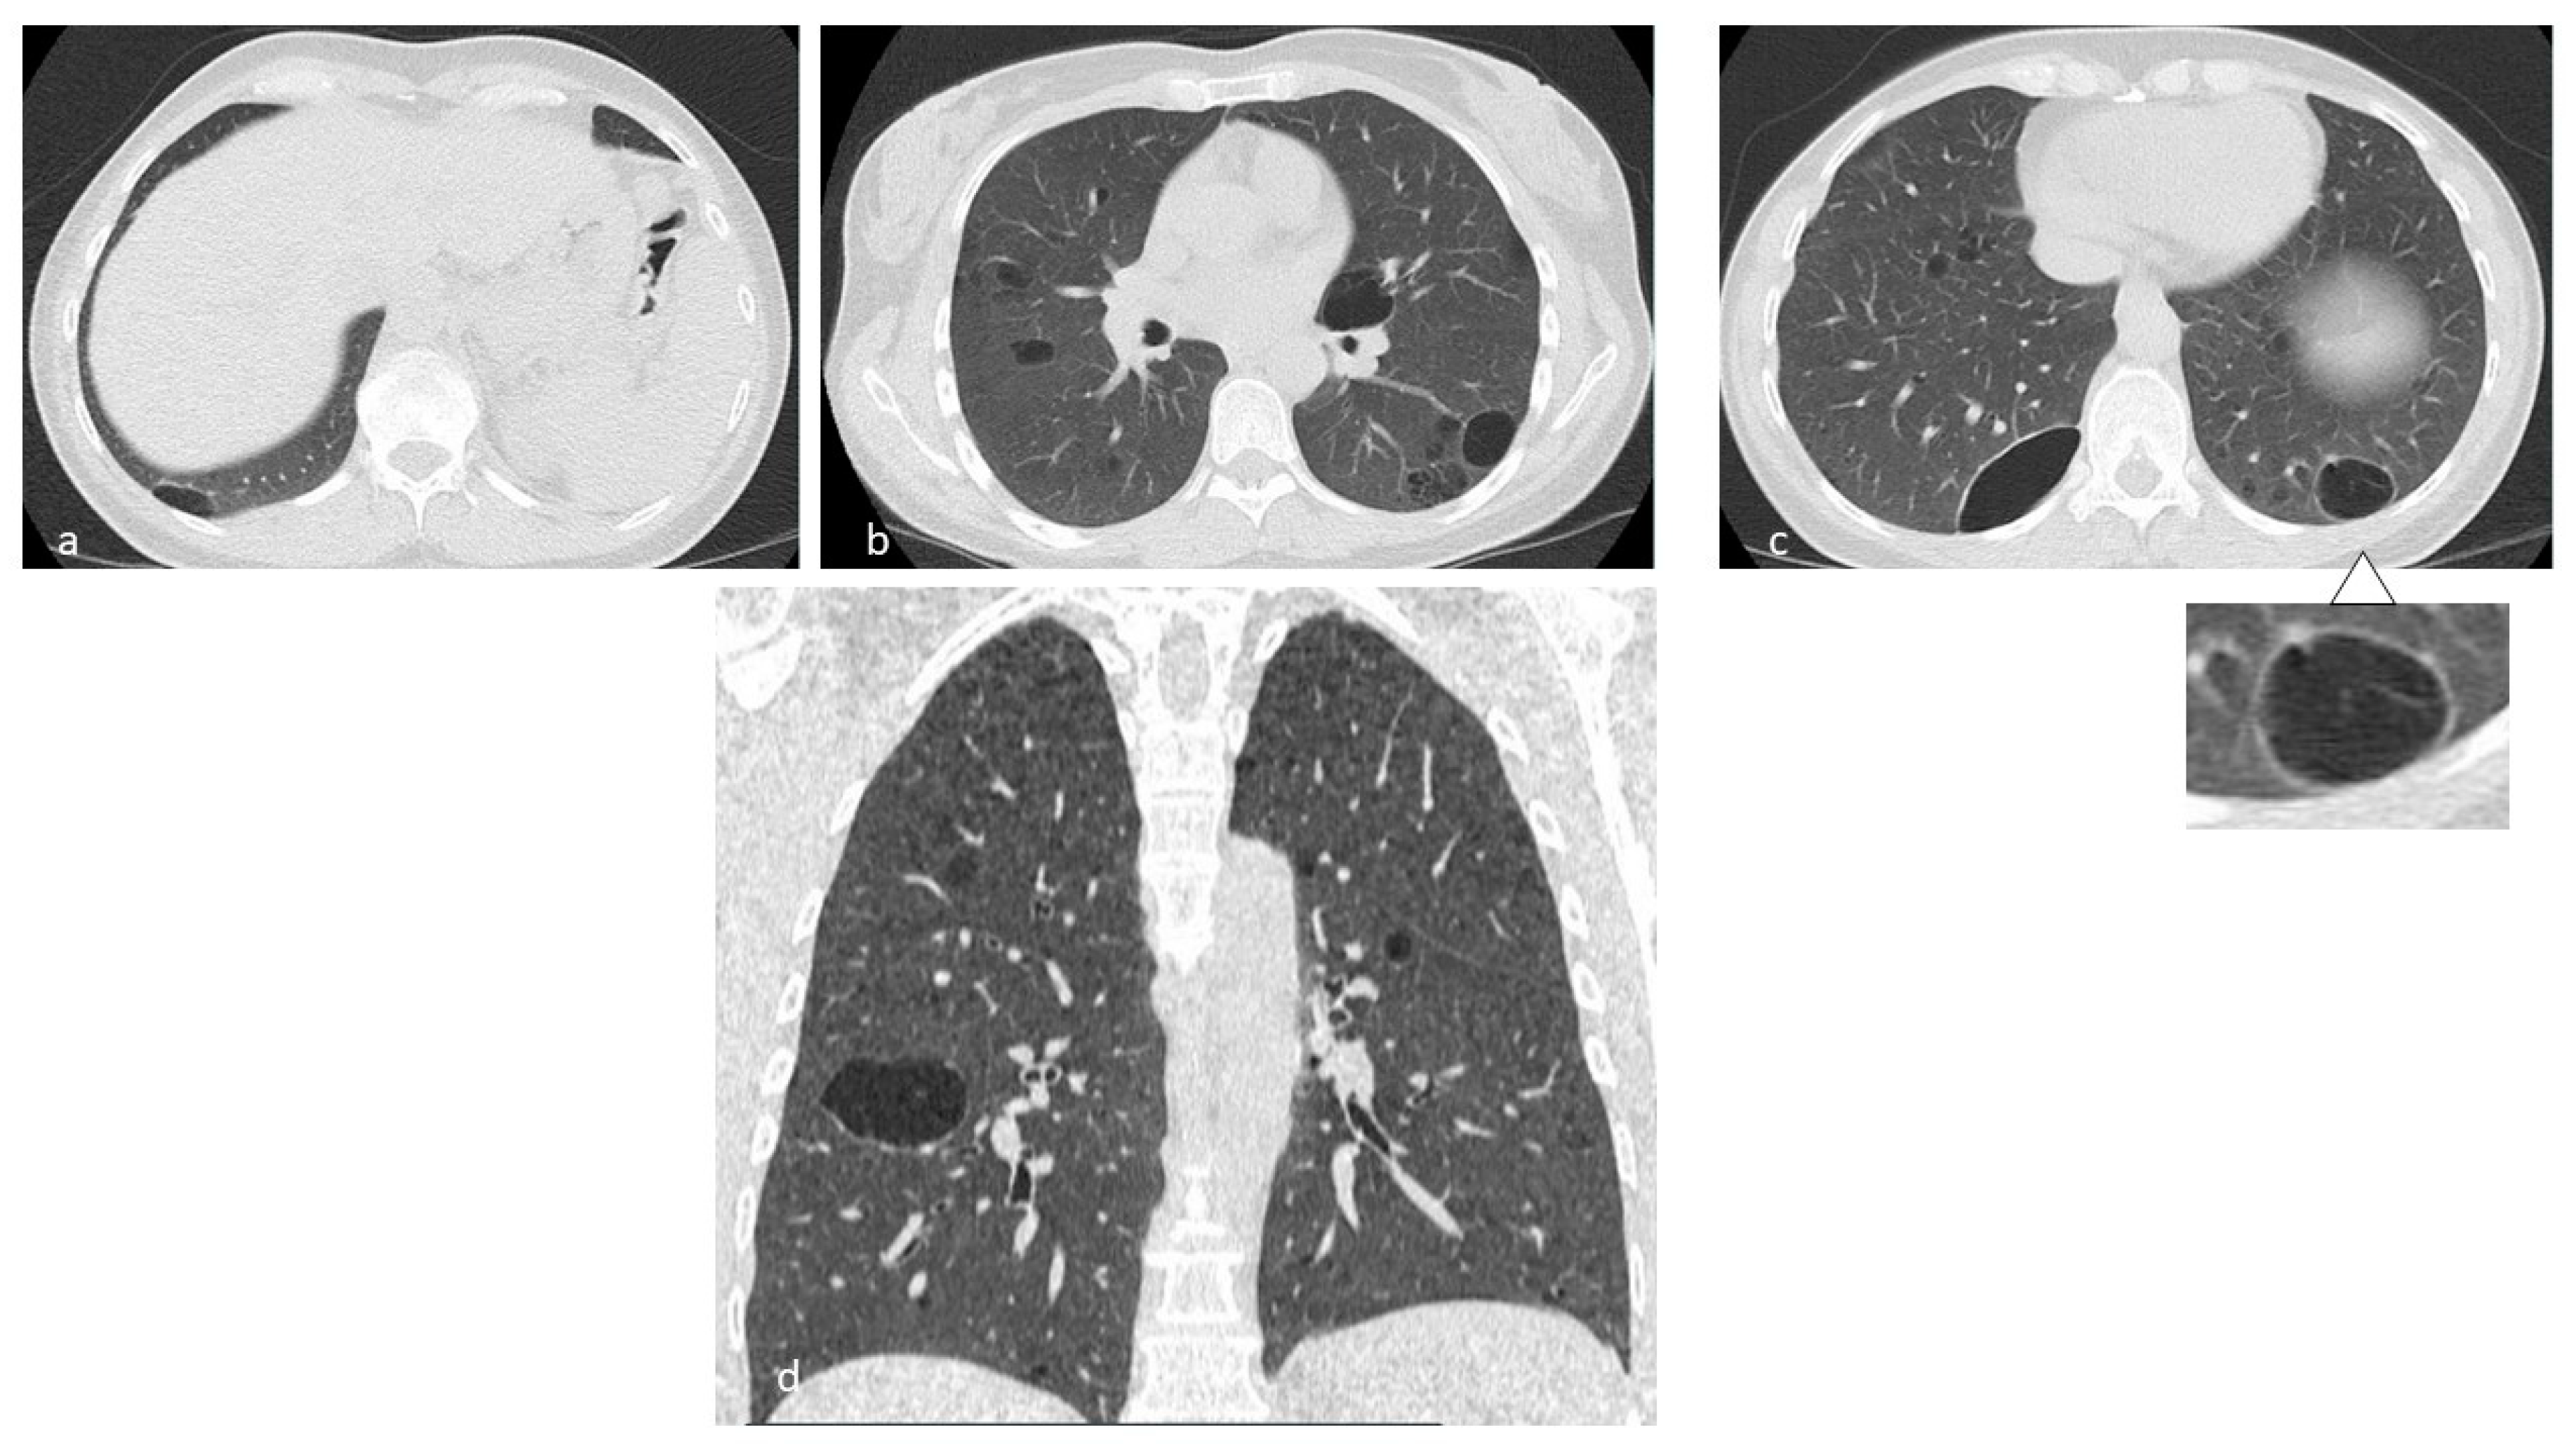

Figure 1. In LCH, cysts may origin from the cavitation of nodules (a,b) and can be isolated or confluent, and are mainly located in the middle and superior lobes, with typical sparing of costophrenic angles. Multiplanar reconstruction (MPR) in the sagittal (c) and coronal plane (d).

Morphologically, these bronchioles-centric lesions evolve from micro- and macro-nodules—with a highly represented cellular component—to lesions with low cellularity, often star-shaped, with fibrotic scar [9]. In the advanced stages of the disease, the nodule’s cavitation is the most common evolution—resembling a cystic appearance (Figure 1).

Lung cysts, which are the most advanced expression of the evolution of LCH, may vary in size from one to several centimeters; they occur with thick wall and “bizarre” morphology, having poli-lobulated or clover-leaf contours, in contrast to the more uniform and bland cysts typical of other diffuse cystic lung diseases, such as LAM; the cysts have also a wide distribution (Figure 2), with a predominance in the lung apices and the medium regions, typically sparing costophrenic angles (Figure 3); this distribution is one of the diagnostic keys that distinguishes LCH from LAM [10] (Figure 4). Another helpful clue is the sparing of the medial tips of medial lobe and lingula; lung volumes are normal or increased, an unusual appearance when reticular opacities or honeycombing occur. Frequently, cysts are the only alteration found in HRCT scans, but in most cases small nodules are also detectable.